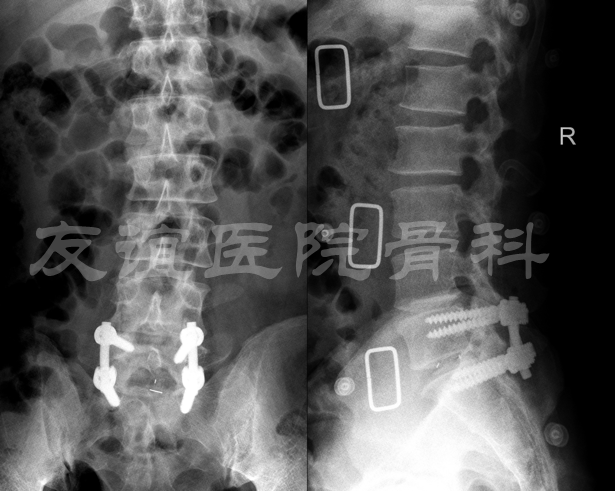

2018年4月12日在全麻下行“腰椎后路椎间盘摘除,椎间融合固定(L5-S1),椎板间固定非融合术(L4-5)”术后患者术前左下肢疼痛麻木症状明显好转,术后X光见图4,术后顺利出院。术后1年随访的X光(图5A B)和术后即可比较无明显差别,腰椎核磁共振提示:L5-S1椎间盘已经被清除,神经根压迫得到明显缓解;L4-L5椎间盘突出已经明显缓解,且位置良好。术后1年临床效果满意,患者症状明显改善,左下肢腿疼腿麻的症状已经消失,已经正常上班工作。

图4:术后3天X光正侧位片